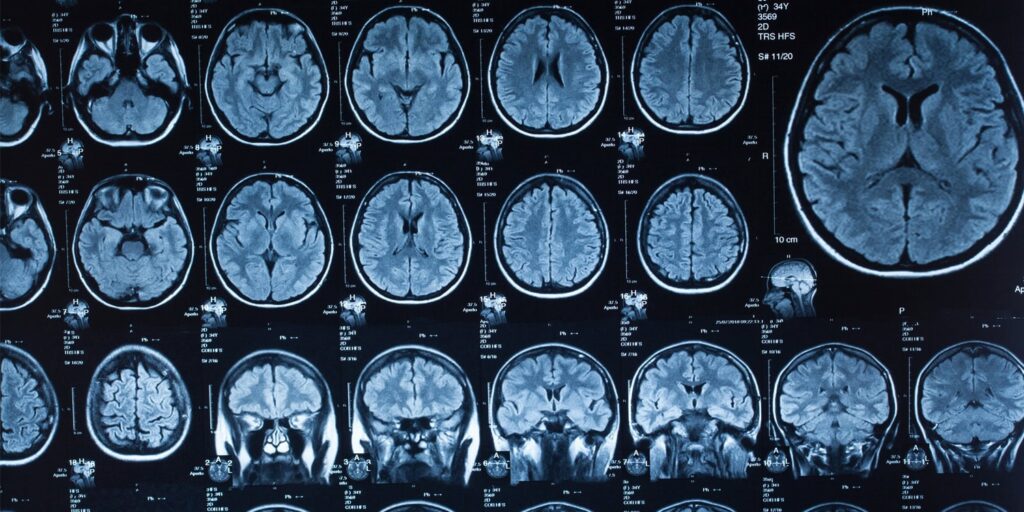

Para construir essa trajetória ao longo da vida, os pesquisadores reuniram dados de nove conjuntos distintos de neuroimagem, totalizando 4.216 indivíduos com idades entre zero e 90 anos. Desse grupo, foram analisados 3.802 exames de indivíduos neurotípicos para estabelecer um modelo padrão de desenvolvimento. A equipe utilizou imagens por difusão, um tipo de ressonância magnética que rastreia o movimento das moléculas de água no tecido cerebral, permitindo mapear os tratos de substância branca, responsáveis por conectar diferentes regiões do cérebro.

Em seguida, os pesquisadores aplicaram a teoria dos grafos para analisar a organização dessas redes cerebrais, calculando doze métricas específicas para descrever a topologia do cérebro, ou seja, a forma como as partes da rede estão organizadas e conectadas. Entre as métricas principais estavam a eficiência global, que mede a facilidade com que a informação circula por toda a rede, e a modularidade, que avalia o quão bem o cérebro se divide em comunidades especializadas e relativamente independentes.